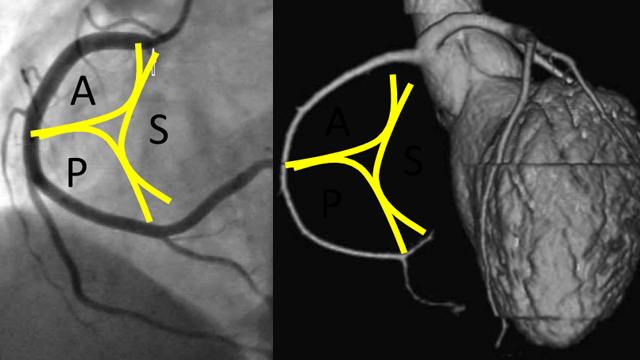

• EBC MAIN - the European Bifurcation Club Left Main Coronary Bifurcation Study

• Clinical Outcomes after Physiology-Guided Treatment of Coronary Bifurcations